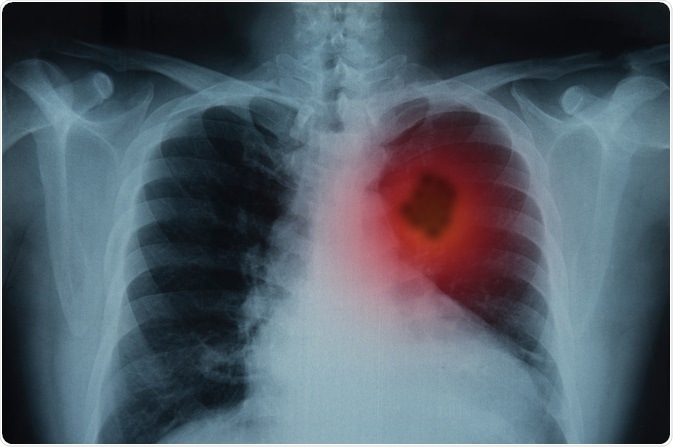

Lung Cancer

Image Credit: create jobs 51/Shutterstock.com